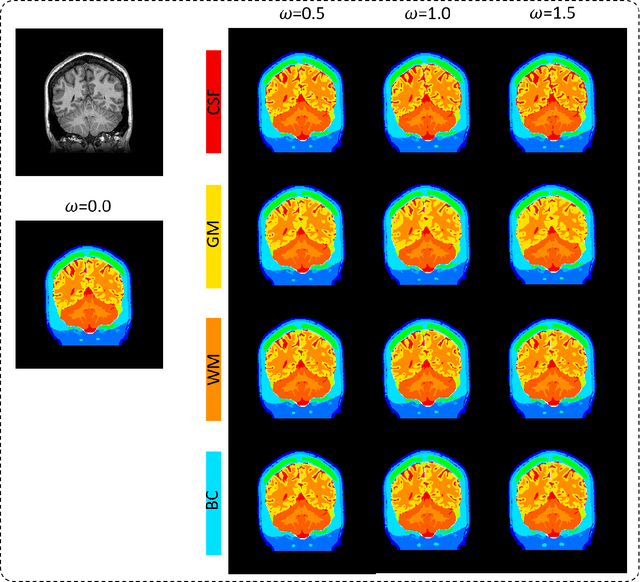

Abstract:In several diagnosis and therapy procedures based on electrostimulation effect, the internal physical quantity related to the stimulation is the induced electric field. To estimate the induced electric field in an individual human model, the segmentation of anatomical imaging, such as (magnetic resonance image (MRI) scans, of the corresponding body parts into tissues is required. Then, electrical properties associated with different annotated tissues are assigned to the digital model to generate a volume conductor. An open question is how segmentation accuracy of different tissues would influence the distribution of the induced electric field. In this study, we applied parametric segmentation of different tissues to exploit the segmentation of available MRI to generate different quality of head models using deep learning neural network architecture, named ForkNet. Then, the induced electric field are compared to assess the effect of model segmentation variations. Computational results indicate that the influence of segmentation error is tissue-dependent. In brain, sensitivity to segmentation accuracy is relatively high in cerebrospinal fluid (CSF), moderate in gray matter (GM) and low in white matter for transcranial magnetic stimulation (TMS) and transcranial electrical stimulation (tES). A CSF segmentation accuracy reduction of 10% in terms of Dice coefficient (DC) lead to decrease up to 4% in normalized induced electric field in both applications. However, a GM segmentation accuracy reduction of 5.6% DC leads to increase of normalized induced electric field up to 6%. Opposite trend of electric field variation was found between CSF and GM for both TMS and tES. The finding obtained here would be useful to quantify potential uncertainty of computational results.